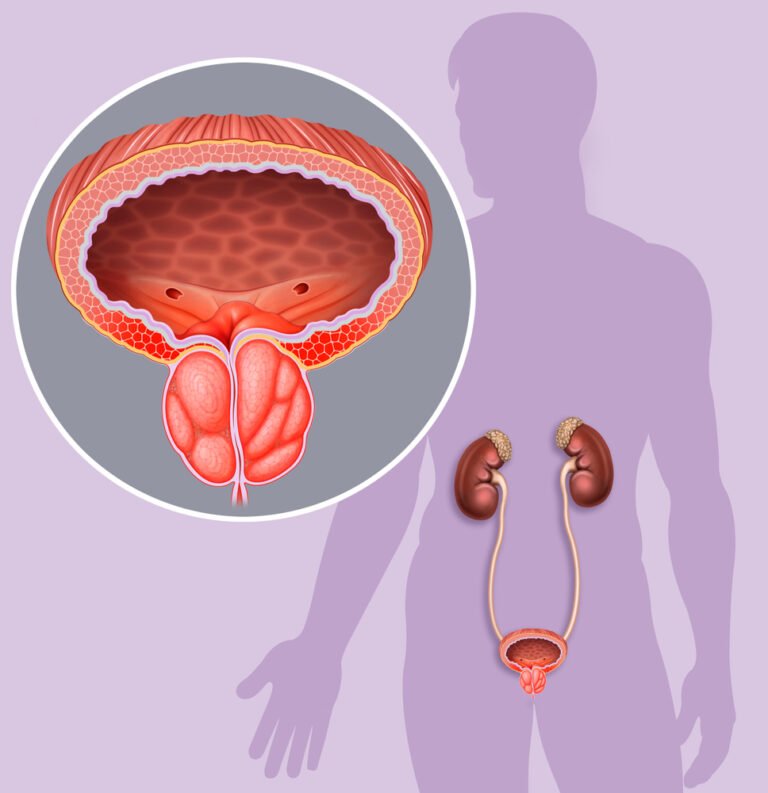

Tekanan yang terus-menerus pada area perineum bisa menyebabkan peradangan kronis pada kelenjar prostat. Minimnya aktivitas fisik setiap hari dapat memperlambat proses metabolisme tubuh dan meningkatkan kemungkinan terjadinya obesitas yang berbahaya.

Kebiasaan menunda untuk buang air kecil dapat menyebabkan tekanan berlebihan pada otot-otot saluran kemih. Jika ini terus berlangsung, dapat mengakibatkan pembengkakan yang mengganggu fungsi normal organ reproduksi pria.

Berpakaian dalam yang terlalu ketat juga dapat meningkatkan suhu di sekitar area genital. Suhu tinggi yang terperangkap bisa memicu peradangan pada sel-sel yang membentuk jaringan kelenjar prostat.

Kebiasaan menahan buang air kecil terlalu lama bisa meningkatkan risiko infeksi pada saluran kemih pria. Urine yang terlalu pekat akibat kurang minum air putih akan mengiritasi lapisan dinding kelenjar prostat.

Bakteri yang terjebak dalam saluran kemih dapat naik menuju prostat dan menyebabkan kondisi medis prostatitis. Pria sebaiknya memenuhi kebutuhan cairan harian agar proses pembuangan sisa metabolisme tubuh berjalan dengan lancar.

Kekurangan cairan tubuh membuat sistem drainase alami pada area genital menjadi sangat tidak optimal. Sirkulasi nutrisi menuju sel-sel prostat juga terhambat sehingga menurunkan kemampuan regenerasi sel secara alami.